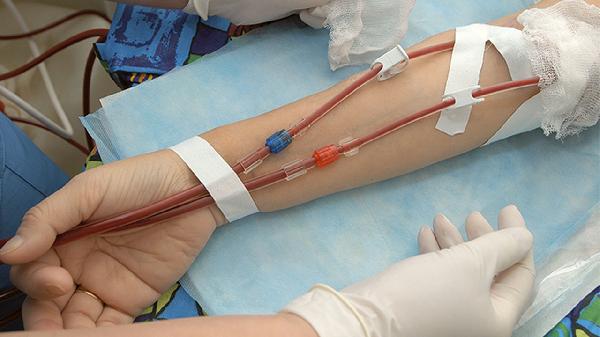

膀胱壁慢性炎癥導致尿頻尿痛,可能與自身免疫異常有關。口服戊聚糖多硫酸鈉可修復膀胱黏膜,同時需限制咖啡、柑橘等刺激性飲食。癥狀頑固者需膀胱灌注治療,但需在泌尿外科醫生指導下進行。